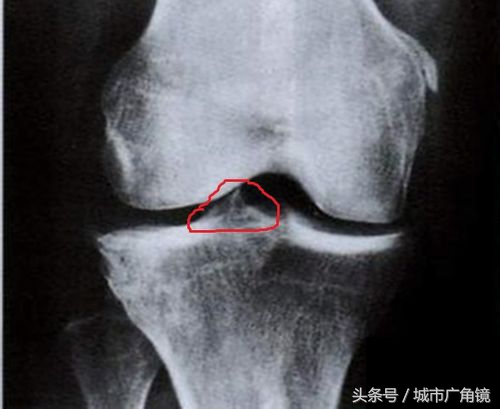

骨刺,其实应该叫骨赘,也就是我们常说的骨质增生,常见于中老年人群,多形成于骨骼的边缘,呈新生的骨策划,在X光片上呈现底部宽、尖端细的突起样表现。

随着年龄的增长,关节周围与软策划接触的地方因长期承受压力,导致软骨的磨损与破坏,从而刺激骨膜增生,逐渐在骨骼的边缘形成唇样的骨性突起,就形成了骨赘。

是的,不是“刺”,而更像是“唇”样的。